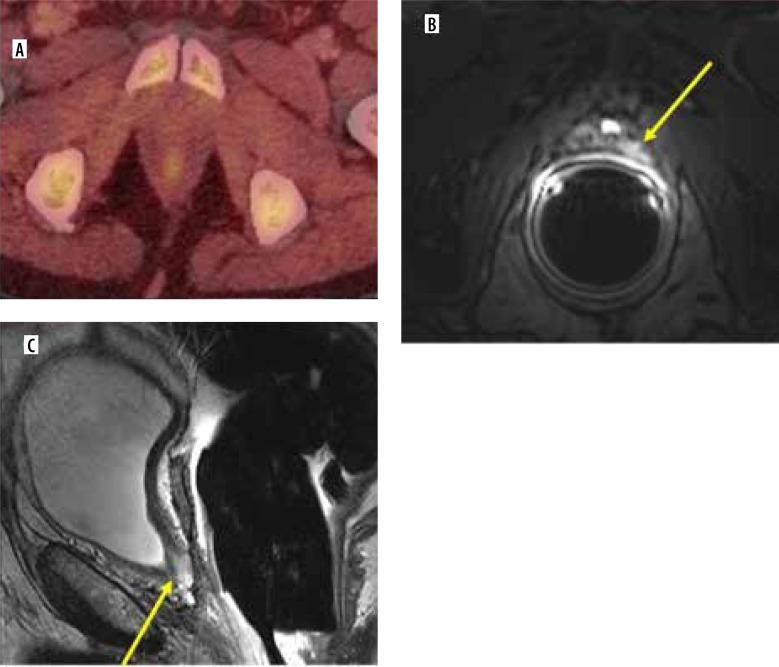

The primary objective of this study was to evaluate the discriminatory utility of magnetic resonance imaging (MRI), F-fluciclovine positron emission tomography (PET), maximum standardized uptake value (SUV), prostate-specific antigen (PSA), and combinations of these diagnostic modalities for detecting local prostate cancer recurrence in the setting of rising PSA after radical prostatectomy.

The study found that MRI had the highest concordance (96%), sensitivity (100%), specificity (91%), positive predictive value (93%), and negative predictive value (100%) among the diagnostic modalities. The AUC for MRI was 0.9545, indicating a high discriminatory ability for detecting prostate cancer local recurrence. When combined, PET and SUV (cut-off value of 2.85) showed an improved performance compared to using them individually, with an AUC of 0.8925.

The analysis suggests that MRI is the most effective imaging modality for detecting local prostate cancer recurrence, with F-fluciclovine PET and SUV also showing promising combined results. PSA has moderate discriminatory utility at follow-up but can still provide valuable information in detecting prostate cancer recurrence. Further research and recent references are needed to support these findings.